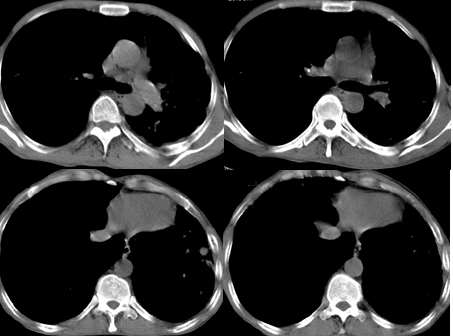

男,58岁,胸痛、咳嗽一周,无痰血;否认其他特殊病史

两肺空洞,纤维化,两中下肺野支气管播散灶及点状钙化,纵隔移位,淋巴结钙化,可符合慢纤洞。

右下肺肺纹理纤细,并可见囊柱样改变,不除外先天性囊肿及支气管扩张。

两肺结核(空洞,支气管播散灶)并左肺纤维化,支扩,肺大炮,胸膜肥厚粘连。

两侧胸廓不对称,左侧明显变小,两肺上叶可见空洞,纤维条索影,两肺下叶多发斑片状影。考虑两肺上叶继发性肺结核伴两肺下叶支气管播散。

影像;两上肺及左中下肺多个大小不一薄壁不规则空洞,部分空洞可见少量液平,周围拌有条索影,纵隔,心脏左移,两中下肺多发散在小结节以及小囊状阴影。

考虑;慢纤洞伴两肺下叶支气管播散。肺结核合并症---支扩。